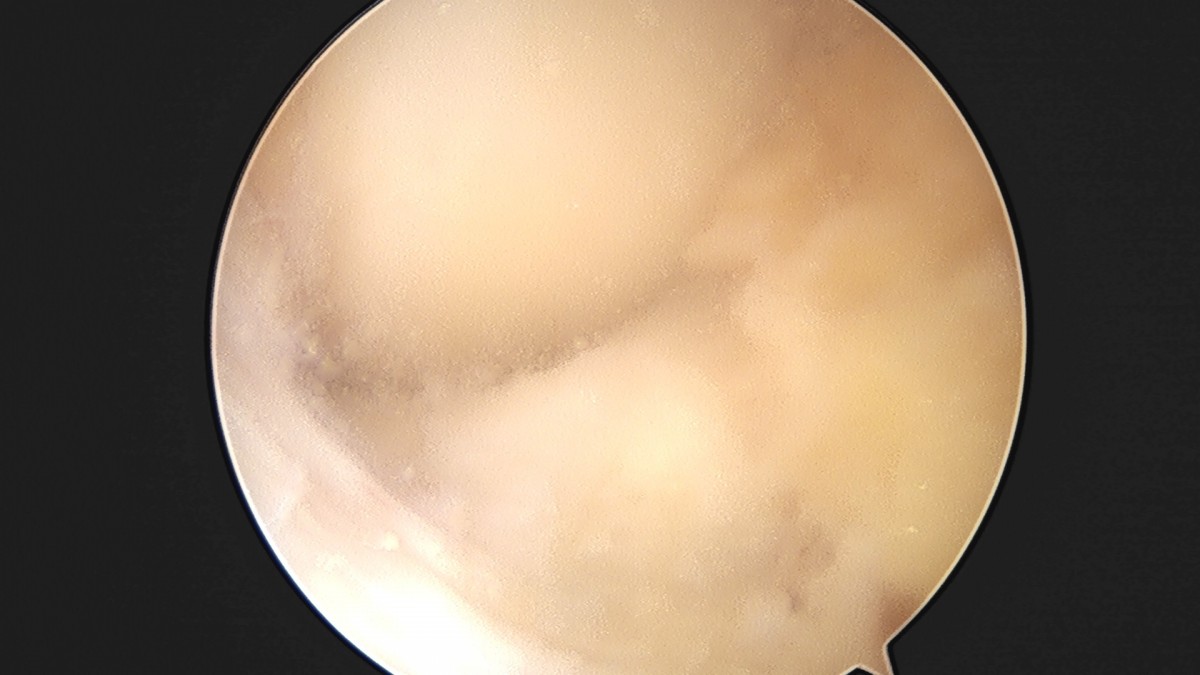

이재상원장님 무릎 반월상 연골판 절제술 조미O 환자

dae765e4d9ac96aee867c9d6292d8784_1758005942_4772.jpg